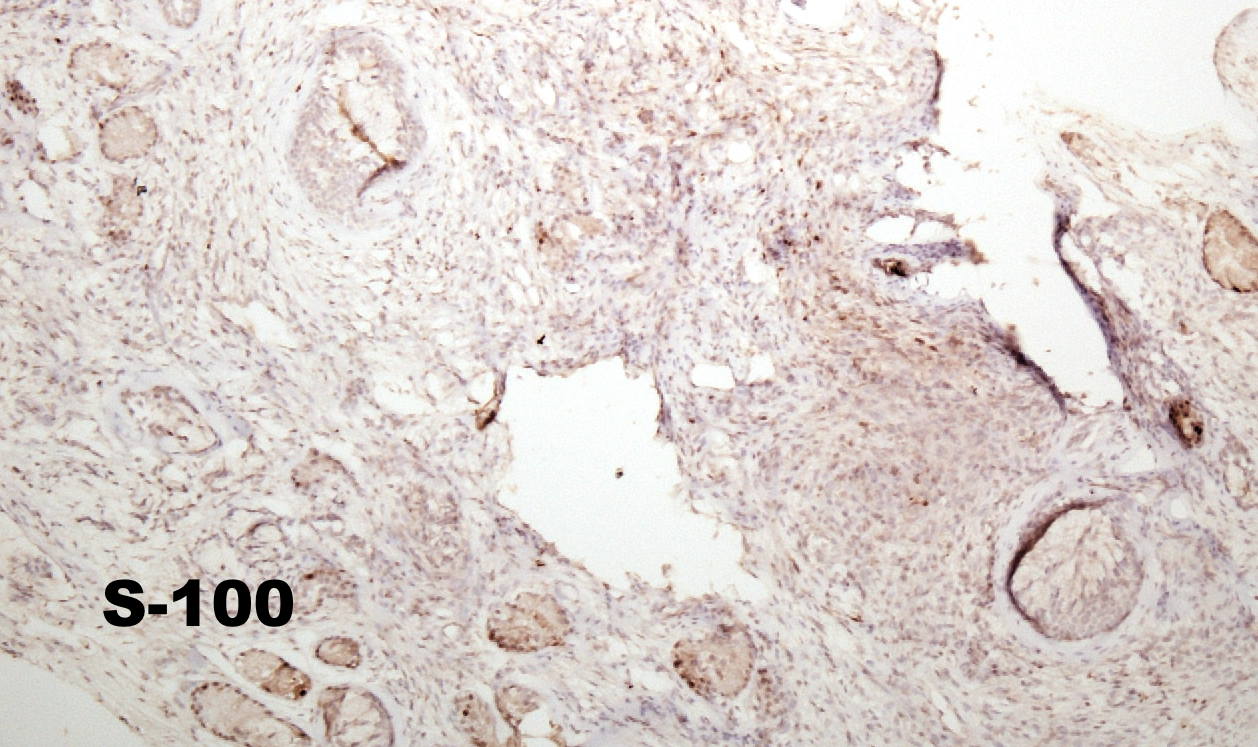

Case history: 17-year-old female with large, solid adnexal mass.

What is the diagnosis?

- Germ cell ...